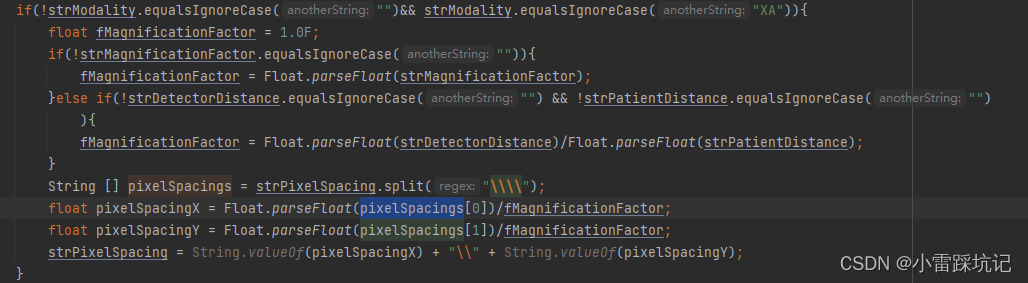

哒哒,最后算像素 pixelSpacings时需要除以这个比例Estimated Radiographic Magnification Factor